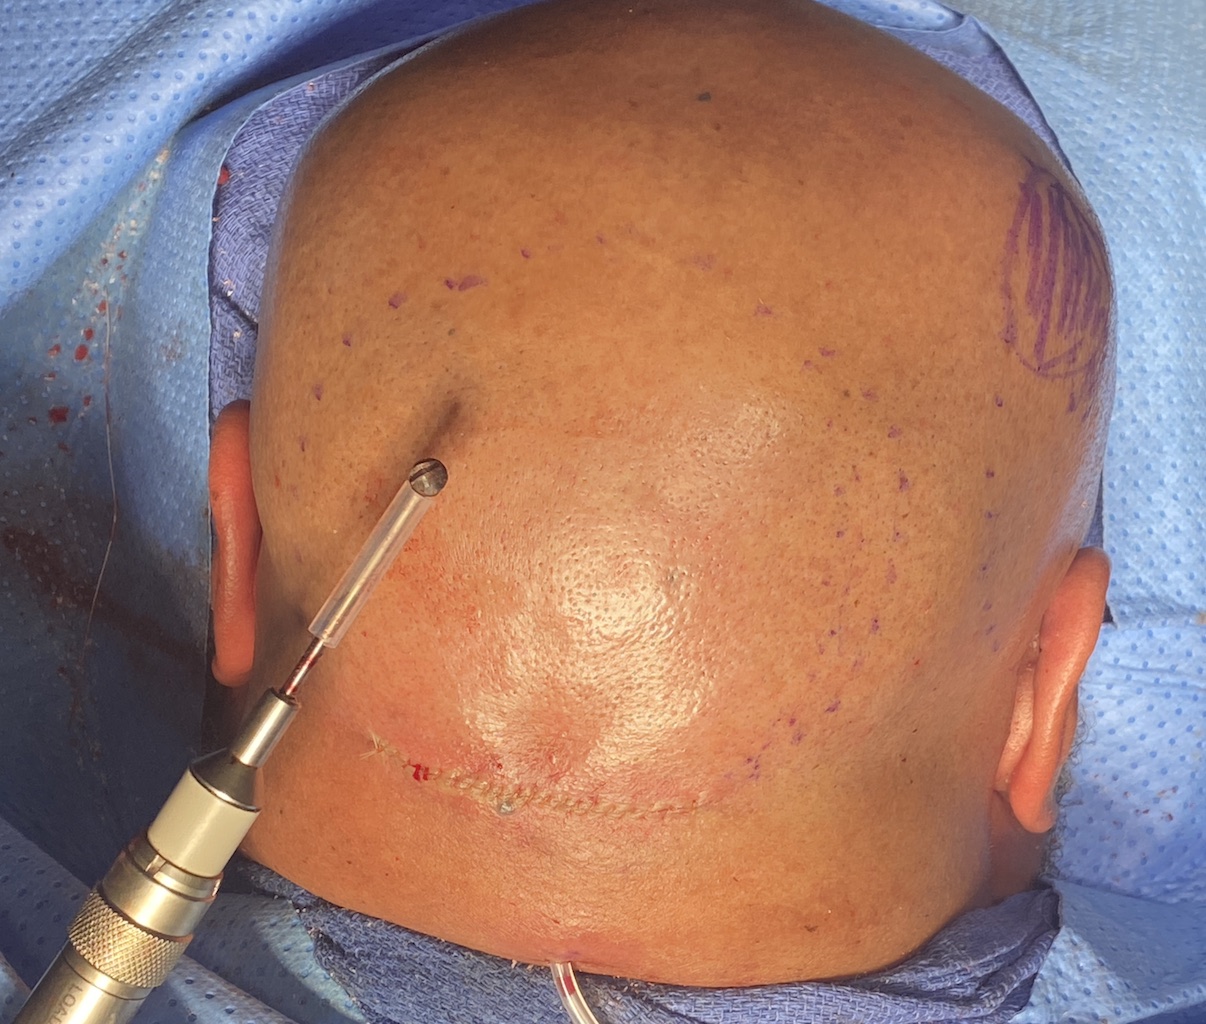

Patient 61

Desire for less wide sides of the head.

Head narrowing surgery performed by removal of posterior temporal muscle through postauricular incisions.

Desire for less wide sides of the head.

Head narrowing surgery performed by removal of posterior temporal muscle through postauricular incisions.